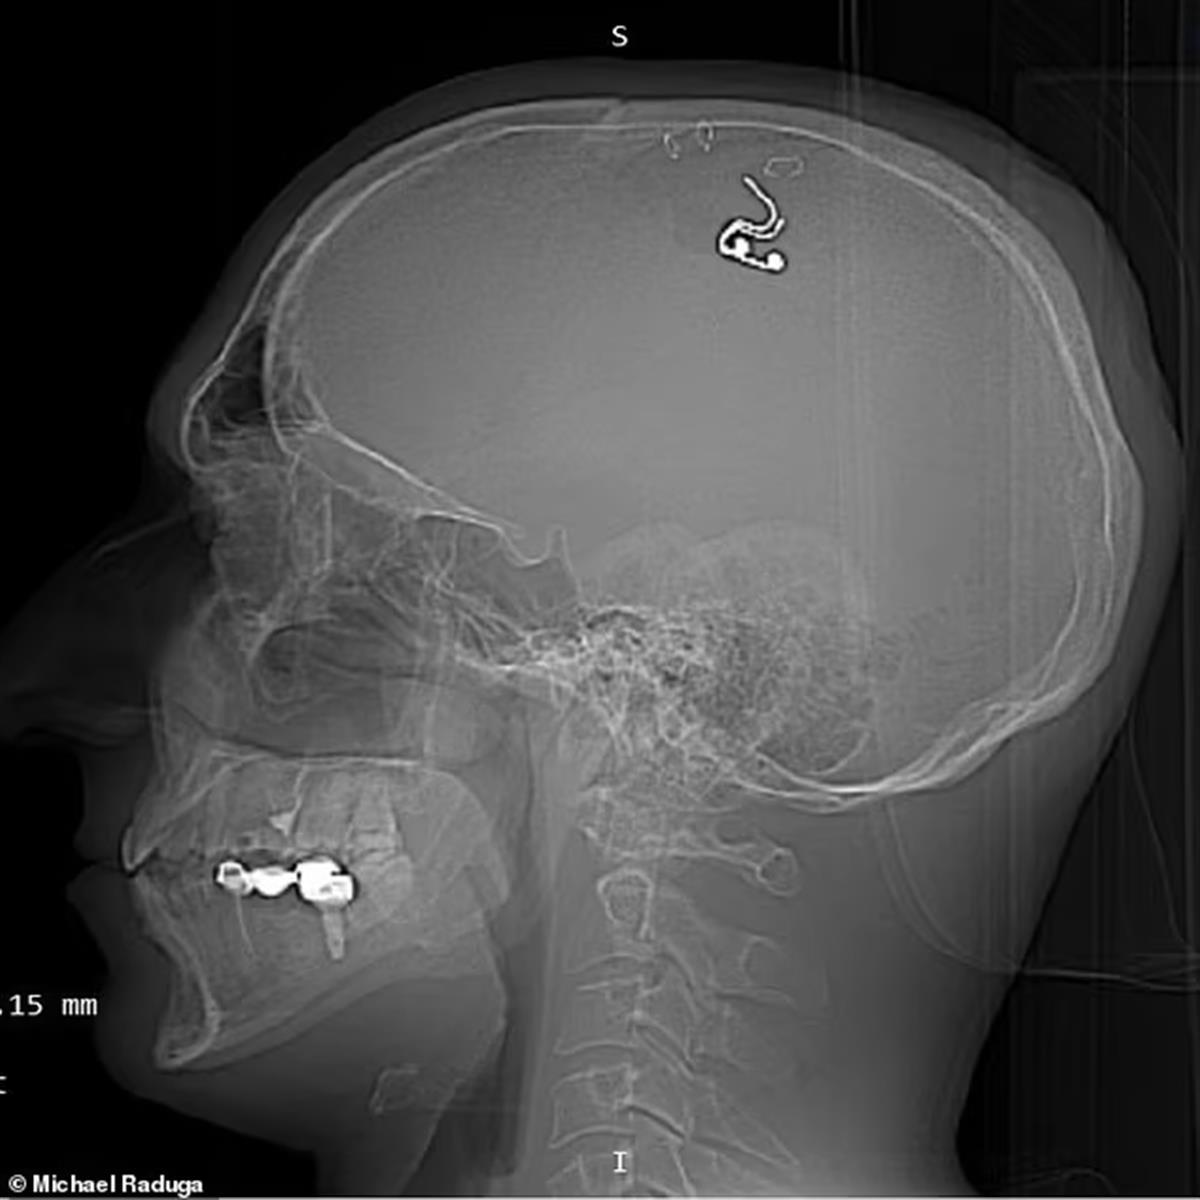

在手术视频中,拉杜加用回形针夹住他的头皮,并用钻头在头骨后部钻孔,随后把一个铂硅植入物植入自己的大脑。整个手术过程中,拉杜加都没有任何专业的神经外科医生指导。由于完全缺乏手术经验,在4个小时的手术中,拉杜加失血近1升,感觉自己几乎要死了。

拉杜加声称,植入物可以帮助他用电来触发梦中的某些动作。然而,手术五周后,拉杜加还是去医院取出了这一植入物。尽管如此,拉杜加仍认为自己进行的这项实验可以帮助人们控制自己的梦境,还将其比作现实版《盗梦空间》。